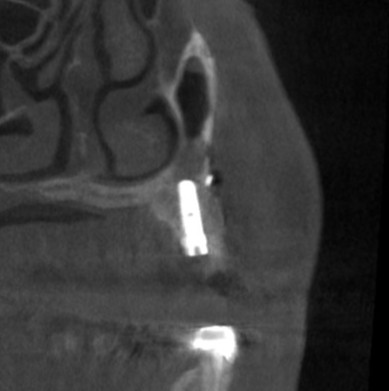

後ろ2本の骨の高さは確保できましたので、インプラント埋入を行ないました。

1本目の部位では、インプラント埋入と同時に、側方に人工骨を補填して骨幅を拡大する造成術を併用して、3本のインプラント埋入が終了しました(下の写真、4段目)。